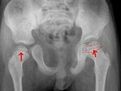

何為骨骺線

骨骺線閉合

這也就是說,我們在青春期發育後,骨骺線閉合後,就不會再長高了(只考慮長骨),因為長骨不再長了,就是腿,胳膊不再變長。之所以有二十三,竄一竄的說法,是因為是我們可以通過 非長骨的組織來長高一些,尤其是脊椎變長,包括骨和骨間組織 (這個對相當一部分人還是很明顯的) 。骨骺線模糊是表示要閉合了,但是 下肢的閉合會比上肢晚一些。男生會比女生晚一些(這也是性發育,激素分泌的效果)。 對於一般人來講二十一,二(男生)也算是最晚的實現了。一定要加強鍛鍊和營養,鍛鍊是良性刺激,會使骨頭更努力的生長,而營養保證了原料的供給。